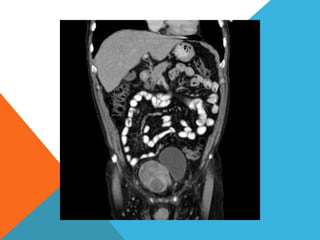

El paciente presentó síntomas de sangrado digestivo y pérdida de peso. Exámenes revelaron gastritis crónica asociada a H. pylori. Un tumor fue descubierto en una colonoscopia normal. La cirugía removió un tumor fibroide solitario, una rara neoplasia mesenquimal que usualmente crece lento y tiene bajo potencial de malignidad. El pronóstico después de la remoción quirúrgica es generalmente bueno.